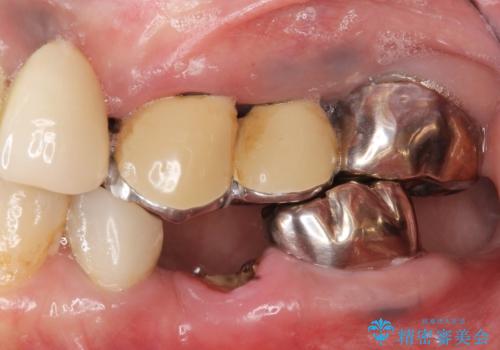

- 「他院で虫歯治療を行っているが、延々終わらず数年経過している。全体的な治療を希望したい。」と全顎的な治療を希望され来院されました。

・再発した虫歯

・銀歯の下にできた虫歯

・根尖性歯周炎

・残根状態の歯

など、虫歯を原因とする問題が多発した状態です。

今後延々と治療を繰り返さないために、全ての銀歯を外し虫歯を丁寧に取り切り、根管治療を行い、残せない歯は抜去を行った上でインプラント治療を行っていくことで全体的な治療を計画していくこととなりました。